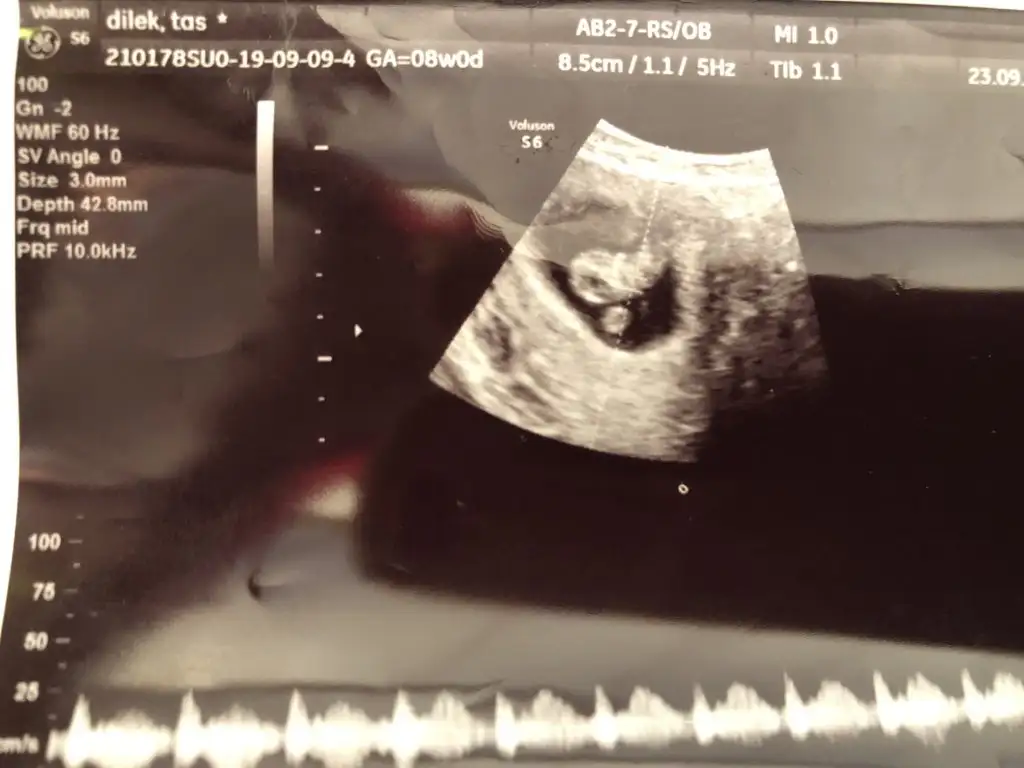

Bize bakar mısınız ❣Saga yakın kız vajinalsa erkek

5 yada 6 yada 8 hafya usg olmalıEki Görüntüle 2538863 Eki Görüntüle 2538863 Eki Görüntüle 2538864 8 haftalık usg görüntüsü kızlar sizce cinsiyeti ne

6 yada 7 hafta usg ise karındansa kız vajinalsa erkekKeseye göre bakar mısınız

Size 7+1 usg cvp yazmıştım 8 hafta usg bakılmıyor kese konumu ama 11 yada 12 hafta nub teorisine bakılıyor

8 haftalık karin dan6 yada 7 hafta usg ise karındansa kız vajinalsa erkek

Burda 7 haftalik6 yada 7 hafta usg ise karındansa kız vajinalsa erkek

Eki Görüntüle 2538863 Eki Görüntüle 2538863 Eki Görüntüle 2538864 8 haftalık usg görüntüsü kızlar sizce cinsiyeti ne